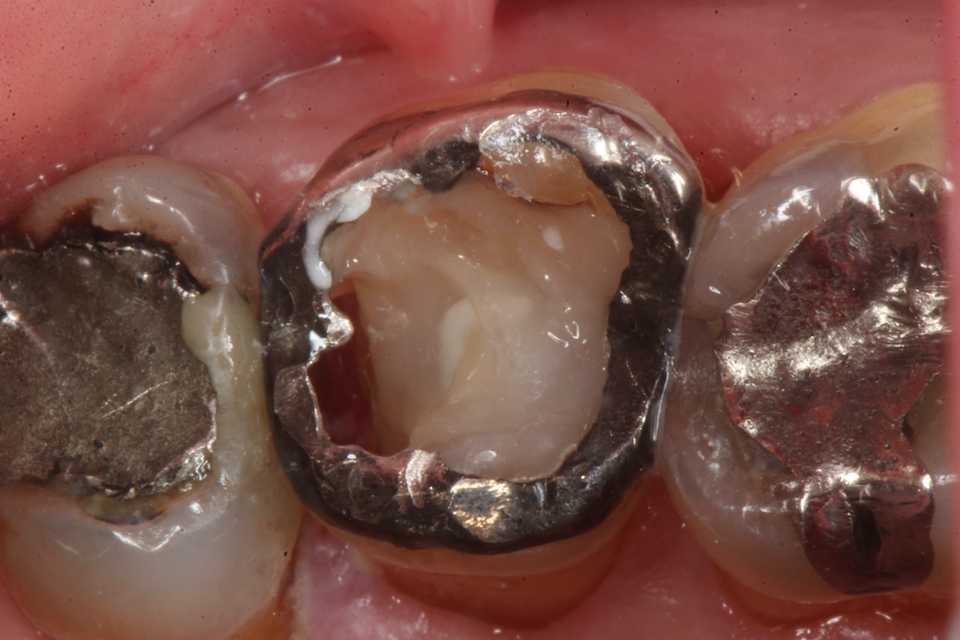

今回の実際の治療法はマージン付近の1mm幅だけは接着シロの為の健全歯質を確保し、露髄しない程度に軟化象牙質を除去し、3MIX+α-TCPで覆罩し、歯質の再硬化を期待するしかない。

再硬化力の弱い他のα-TCP以外のセメントでは失敗する可能性が高い。

直視下ではこんな感じで、患部が見えないのでミラーテクニックが必要になるが、器具も届きにくいので術者も絶望的な気分になる。

患者はこんなものか。。と思うだけだ。通常治療では地獄を見るかもしれない。

3MIX+α-TCP